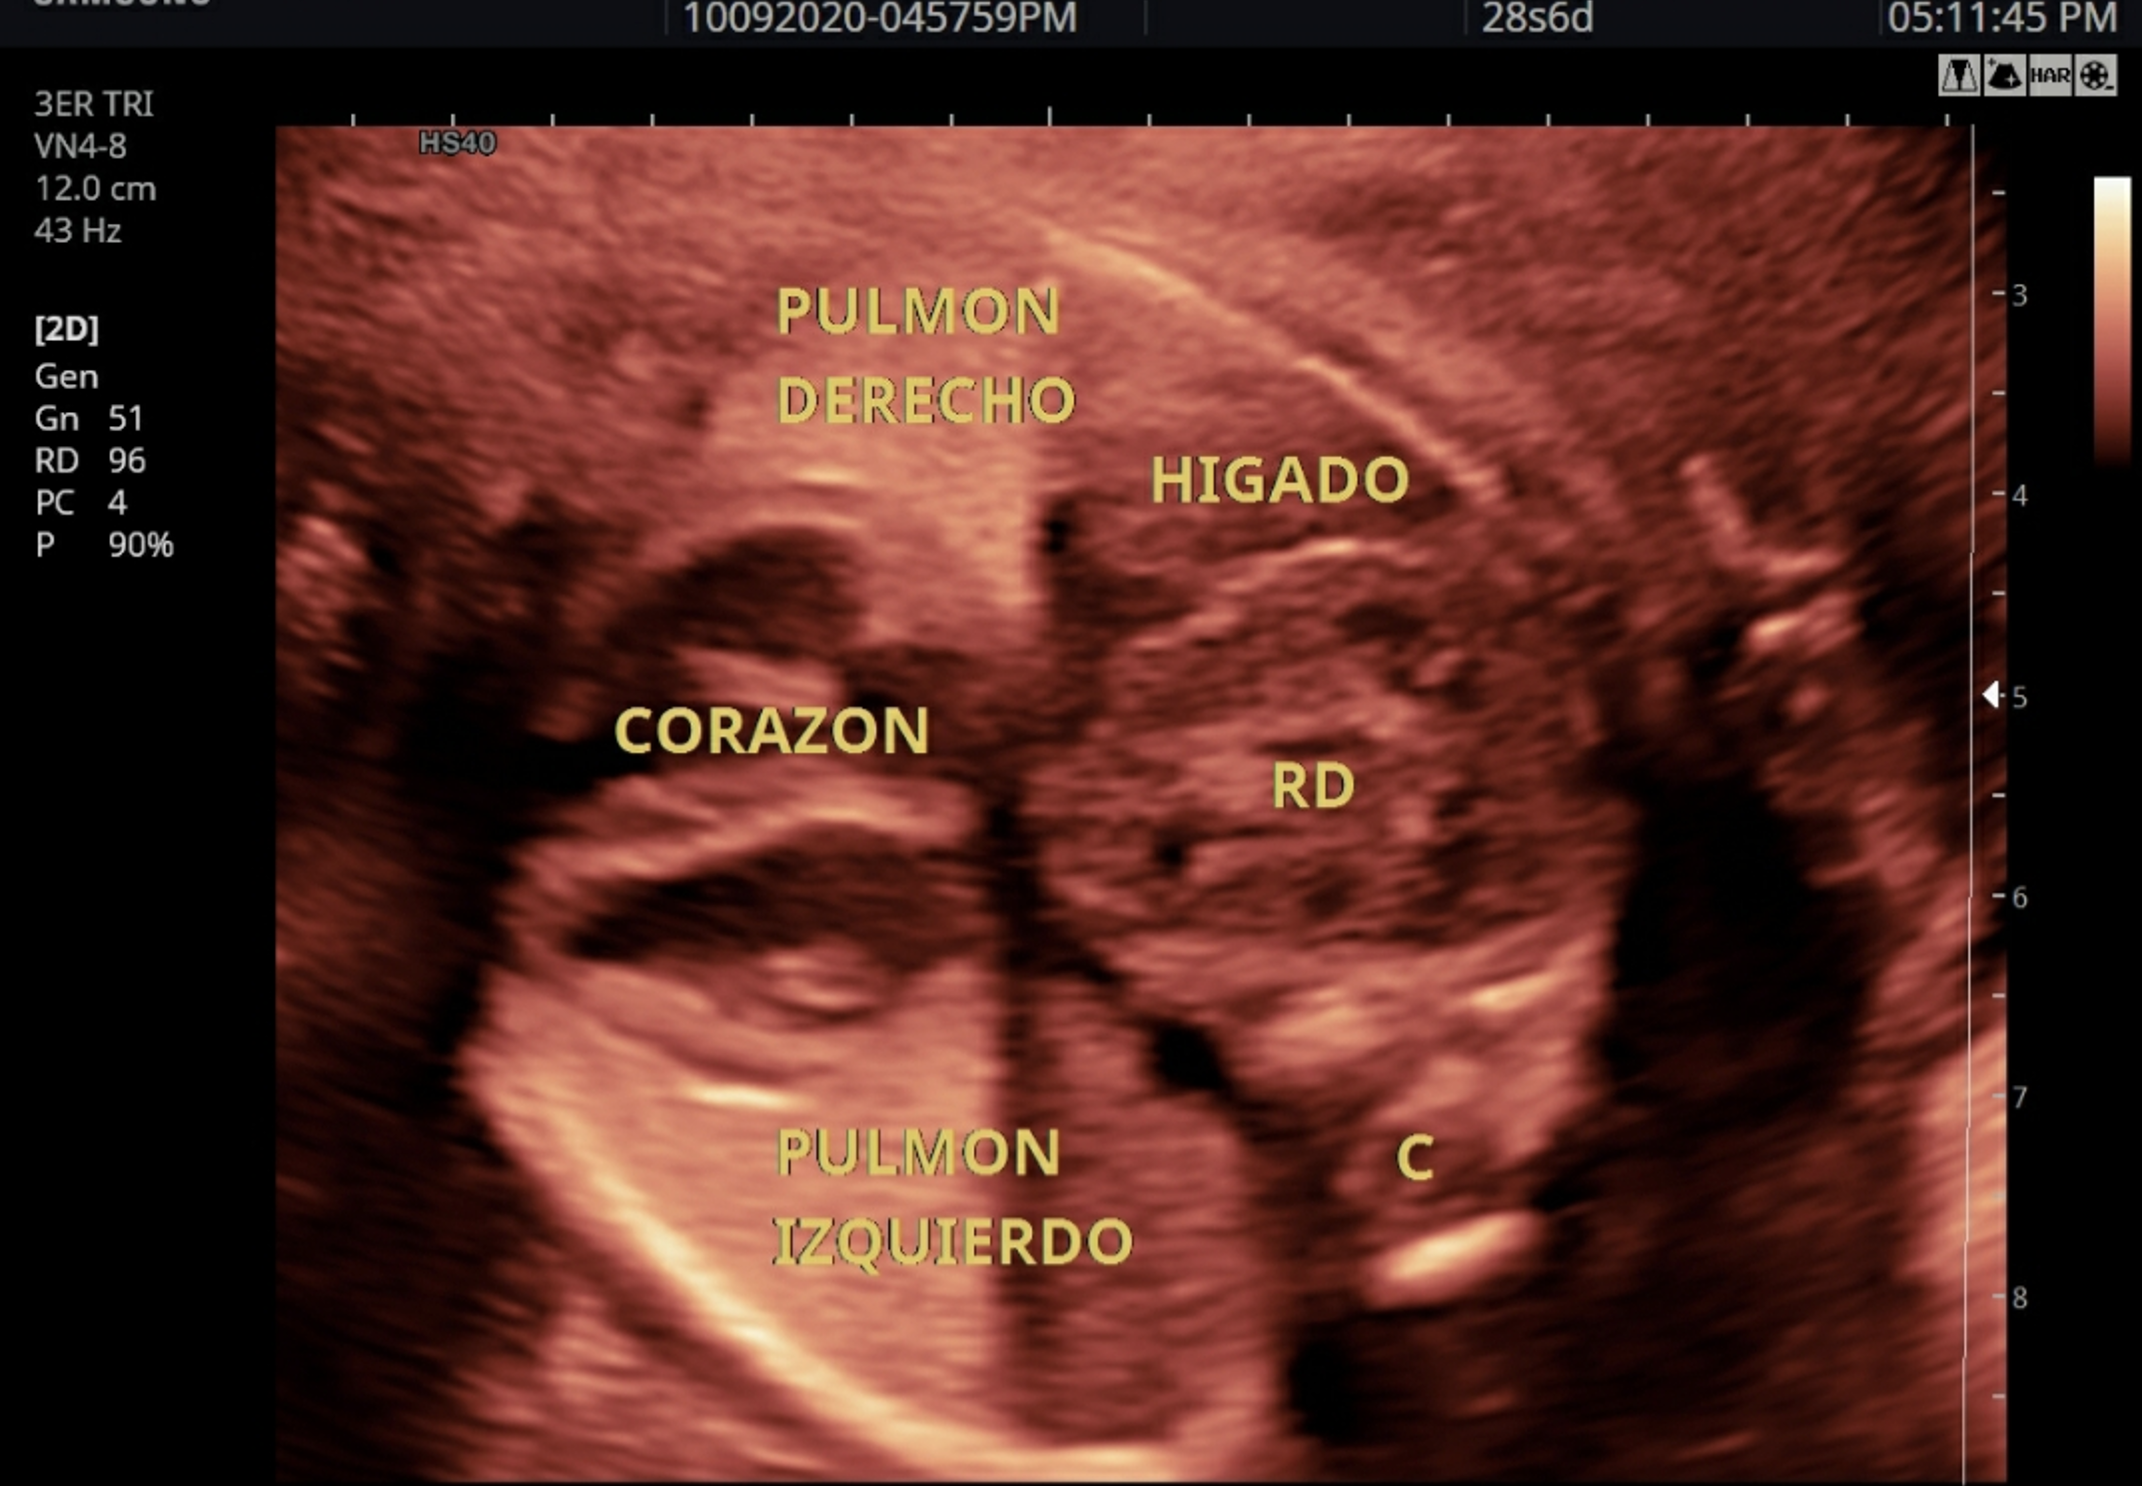

Se presenta el caso de un recién nacido masculino, producto de una unión no consanguínea, cuya madre tenía 24 años, dos gestaciones y un parto previo, sin antecedentes médicos relevantes. Había asistido a ocho controles prenatales en 2022 en los que no se detectaron marcadores de aneuploidías ni alteraciones en la anatomía fetal en las ecografías realizadas en las semanas 11-14 y 22. Sin embargo, en la ecografía de seguimiento realizada a las 28 semanas en una unidad de diagnóstico prenatal privada de la ciudad de Cali (Colombia), se observó en el corte subcostal de 4 cámaras cardiacas en el hemitórax derecho una imagen eco-mixta que comprimía el pulmón derecho contra la pared anterior del tórax y desplazaba el corazón hacia la izquierda, sin levocardia (Figura 1). Se identificaron dos ecogenicidades diferentes y se determinó que se trataba de un REI en el contexto de una hernia diafragmática. Por lo tanto, se ordenó una resonancia magnética fetal, que se realizó a las 31 semanas y mostró una hernia diafragmática derecha con herniación del hígado en los segmentos VII y VIII, y un riñón derecho intratorácico (Figura 2).